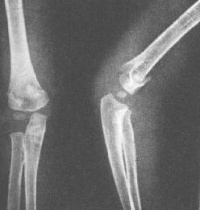

明显外伤史,患肢疼痛,活动受限。X 线片可确定诊断及骨折类上臂短缩、前臂正常上臂正常、前臂短缩型

伸直型肱骨髁上骨折的特点是:骨折线位于肱骨下段鹰嘴窝水平或其上方,骨折的方向为前下至后上,骨折向前成角,远折端向后移位。

屈曲型肱骨髁上骨折的骨折线可为横断,骨折向后成角,远折端向前移位或无明显移位。